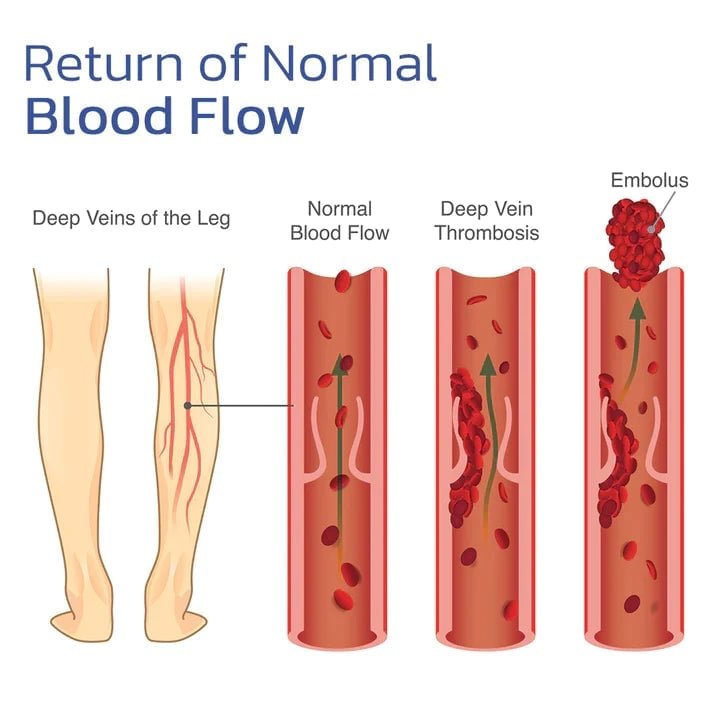

האם ניתן להשתמש בברך כל היום?

כן, בזכות הבד הנושם שלה, היא נוחה ללבישה כל היום ללא אי נוחות.

כן, היא מספקת תמיכה מצוינת לפעילויות מתונות, תוך הפחתת הסיכון לפציעות.

לא, החום נוצר באופן טבעי על ידי חלקיקי טורמלין במגע עם עורכם.